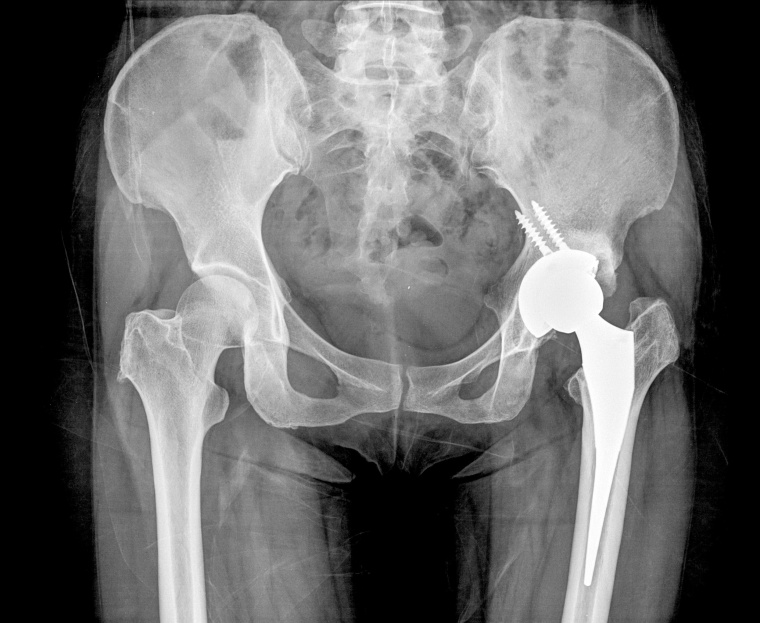

Metallbelastung durch Gelenkimplantate

Die Idee zu dieser Studie entstand auf Grundlage einzelner Fallberichte, deren Veröffentlichungen bereits mehr als zehn Jahre zurückliegen. Darin wurden verschiedene Krankheitsbilder wie zum Beispiel beeinträchtigtes Seh- und Hörvermögen oder Funktionsstörungen des Herz-Kreislauf-Systems, der Schilddrüse und des Zentralen Nervensystems mit erhöhten Cobaltwerten im Blut(serum) der betroffenen Patienten in Verbindung gebracht. „Was diese Patientinnen und Patienten gemeinsam hatten, war, dass sie vor Auftreten dieser Beschwerden mit Hüftendoprothesen mit sogenannten Metall-Metall-Gleitpaarungen versorgt worden waren“, erzählt Anastasia Rakow, Fachärztin für Orthopädie und Unfallchirurgie. „Dies führte und führt immer wieder zu großer Verunsicherung von Patienten mit Endoprothesen, selbst wenn sie mit anderen Implantaten, also ohne Metall-Metall-Gleitpaarungen, versorgt wurden. Zur zentralen Frage unserer Studie wurde es daher, zu untersuchen, ob Metalle aus Endoprothesen überhaupt in der Hirnflüssigkeit nachweisbar sind“, so die Projektleiterin.

Insgesamt 204 Patienten, die zwischen April 2018 und November 2019 in der Charité in Behandlung waren, wurden in die Studie eingeschlossen. Seit 2020 setzt ein Teil der Arbeitsgruppe die themenbezogene Forschung an der Universitätsmedizin Greifswald fort. Das Team aus Orthopäden, Neurologen, Anästhesisten, Labormedizinern und Grundlagenforschern analysierte die Proben von 102 Patienten mit verschiedenen Gelenkimplantaten und verglich diese mit den Proben von 102 Patienten ohne Prothesen. Neben Cobalt und Chrom wurden auch Titan, Niob, Zirkonium und weitere Metalle untersucht. „Dabei schauten wir uns nicht nur das Blut und das Serum, sondern auch den sogenannten Liquor, also das Nervenwasser, an“, erklärt Rakow, die an der Unimedizin Greifswald auch für Implantatsicherheit in der Endoprothetik zuständig ist. Das Forschungsteam hat speziell untersucht, ob die Metalle aus den Implantaten stammen, indem es die Metallwerte mit dem Typ des Implantats in Beziehung gesetzt hat.